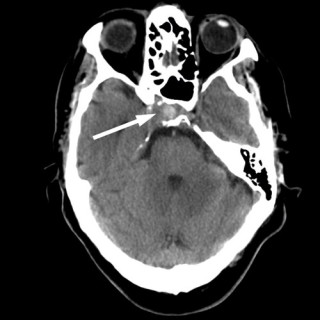

Ved Barneklinikken ved Oslo universitetssykehus, Ullevål, ble det lagt inn en 15 måneder gammel jente med feberperioder, blekhet, forstørret lever og milt. Blodprøver viste anemi, leukopeni, trombocytopeni, høyt ferritinnivå og høyt CRP-nivå. Pasienten viste seg å ha den sjeldne tilstanden hemofagocytisk lymfohistiocytose (HLH), som var utløst av en i Norge meget sjelden infeksjonssykdom, nemlig visceral leishmaniasis. Forfatterne presenterer en problemorientert utrednings- og behandlingsprosess. For en barnelege er dette meget interessant å følge, trolig også for leger innen andre deler av...